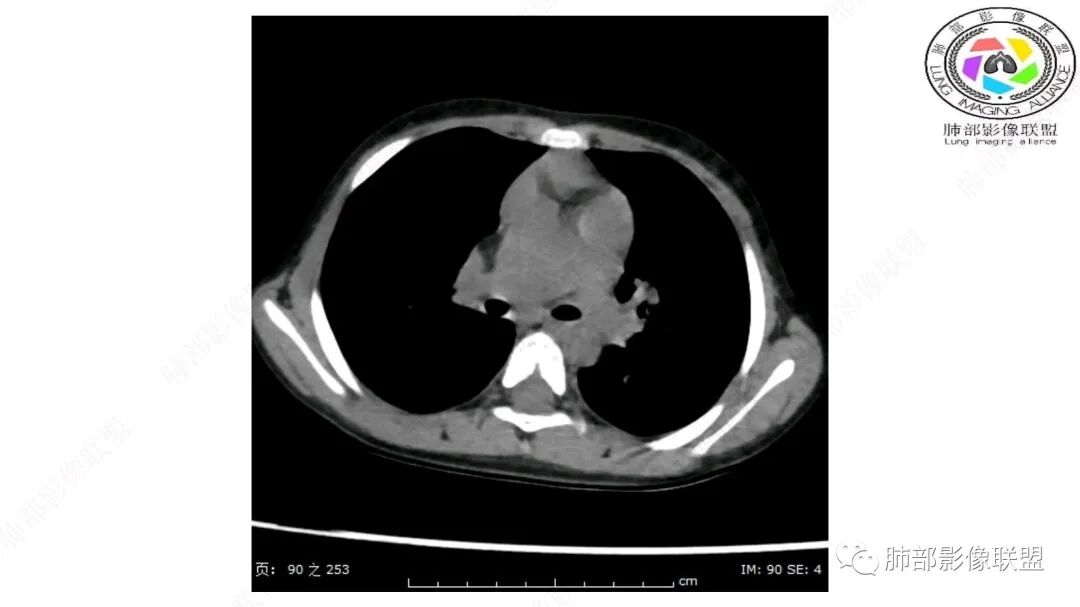

病灶属于交界区,主体位于肺内,占位效应明显,前方突入胸壁,胸腺受压变形,胸膜显示欠清楚;病灶包绕上叶肺动脉;似乎有体动脉供血。符合肺内的点:包绕上叶肺动脉分支;符合纵隔的点:前方似乎突入胸壁,与胸腺关系比较密切,但是与上腔静脉的关系提示病灶不支持纵隔来源,前纵隔的常规会将上腔静脉受压后移、外移,这是不符合的。

内部血管明显,部分病灶密度增高,单纯脂肪瘤不支持。可惜的是:没有提供CT值:是否强化?如果强化,警惕恶性;胸腺肯定不符合,胸腺会将上腔静脉朝后推移。

1.右上肺-纵隔交界区巨块影,主体位于右肺一侧,紧贴胸腺、头臂干、右锁骨下动脉、上腔静脉、奇静脉等,不能分离,但病灶整体边界清楚。注意上述相邻腔静脉等结构未见受压变形,纵隔亦未见明显向左推移,至少提示两点:

2.肺动脉穿行也许是肺内来源最重要支持点!